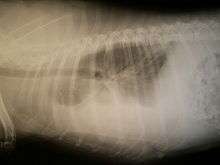

Chest radiography is the preferred means of initial diagnosis for hemothorax.[6] Upright radiography is preferred but supine films may be taken when upright radiography is not feasible due to the clinical situation. Tube thoracostomy may be done prior to imaging when patients have sustained blunt or penetrating thoracic trauma and display unstable hemodynamics, have respiratory failure with absent or decreased breath sounds, show tracheal deviation, or have serious penetrating injuries.[1] In upright radiography, hemothorax is suggested by blunting of the costophrenic angle or partial or complete opacification of the hemithorax, in which the lateral side of the chest appears bright and the lung appears pushed away toward the center; the air-filled lung normally appears as a dark space on radiographic film. In the case of a small hemothorax, several hundred milliliters of blood can be hidden by the diaphragm and abdominal viscera. In supine patients, signs of hemothorax may also be subtle on radiographic film, because the blood will layer in the pleural space, and can be seen as a haziness in one half of the thorax relative to the other side.